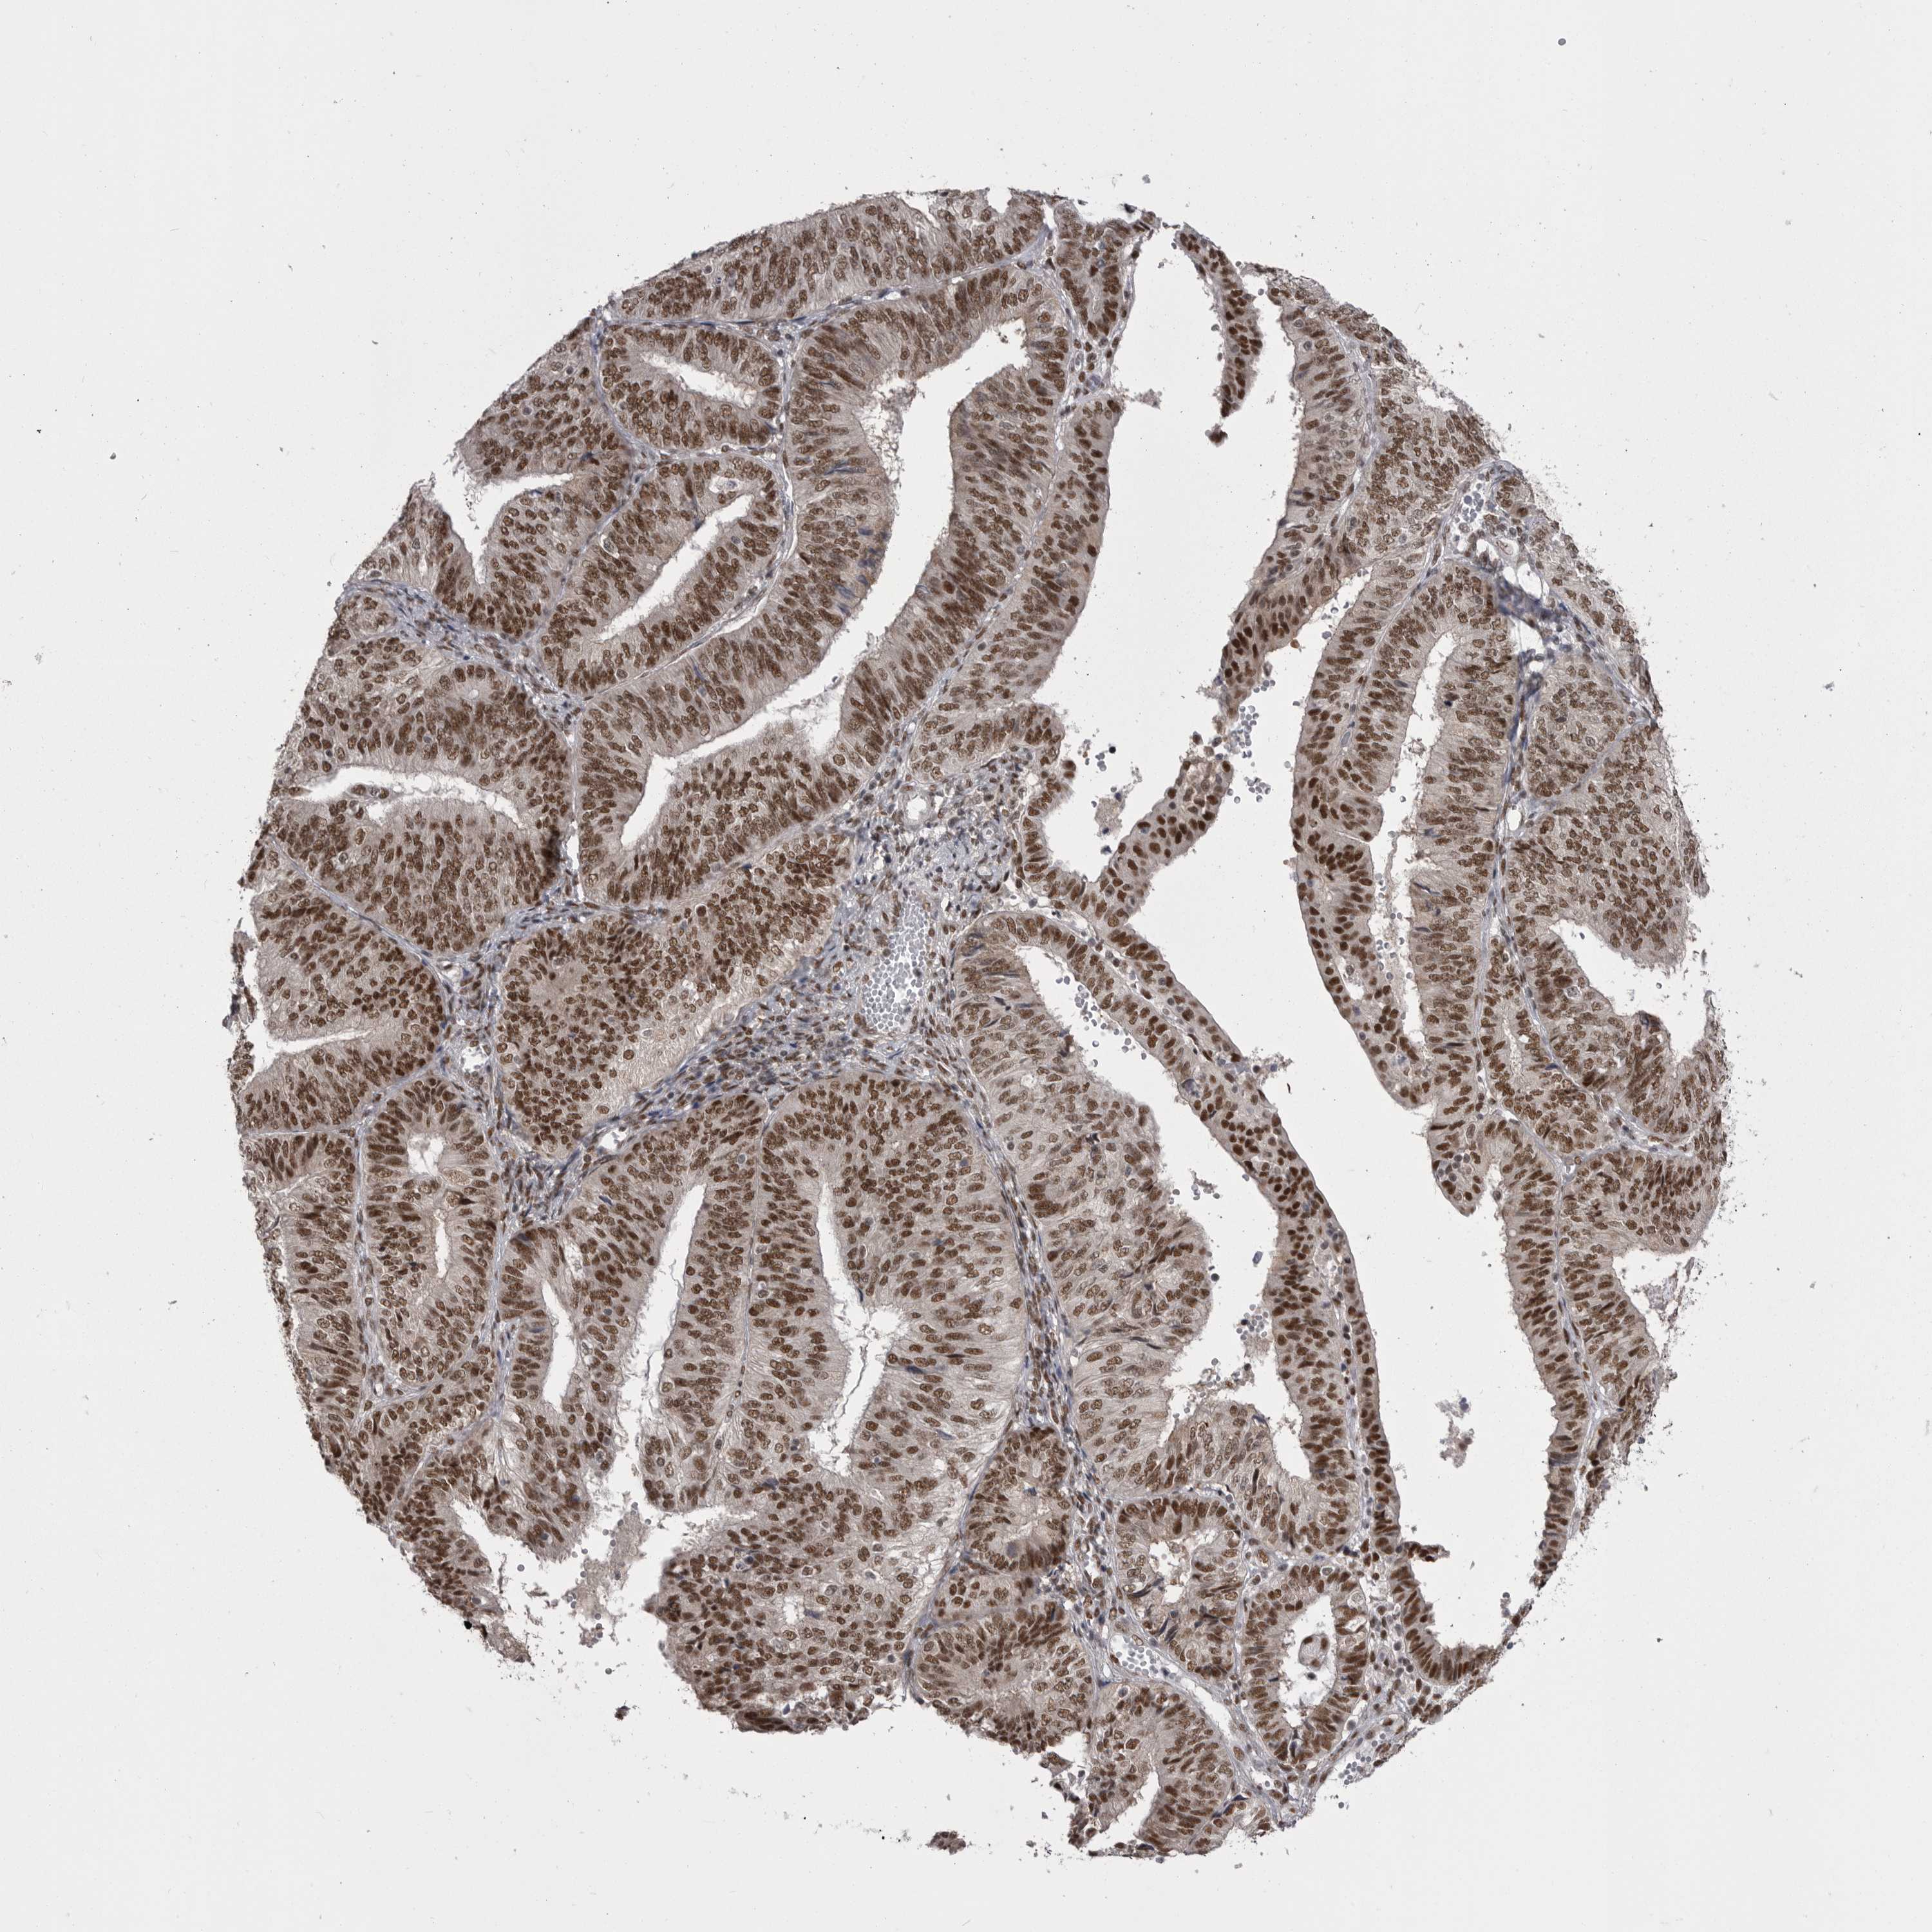

ENDOMETRIAL CANCER - Protein expressioni

A mouse-over function shows sample information and annotation data. Click on an image to view it in a full screen mode. Samples can be filtered based on level of antibody staining by selecting one or several of the following categories: high, medium, low and not detected. The assay and annotation is described here.

Note that samples used for immunohistochemistry by the Human Protein Atlas do not correspond to samples in the TCGA dataset.

Antibody stainingi

Antibody staining in the annotated cell types in the current human tissue is reported as not detected, low, medium, or high, based on conventional immunohistochemistry profiling in selected tissues. This score is based on the combination of the staining intensity and fraction of stained cells.

Each image is clickable and will lead to virtual microscopy that enables deeper exploration of all samples and also displays staining intensity scores, fraction scores and subcellular localization as well as patient and tissue information for each sample.

Antibody HPA051587

Antibody CAB026384

Staining

High

Medium

Low

Not detected

Intensity

Strong

Moderate

Weak

Negative

Quantity

>75%

75%-25%

<25%

None

Location

Nuclear

Cytoplasmic/membranous

Cytoplasmic/membranous,nuclear

Adenocarcinoma, NOS